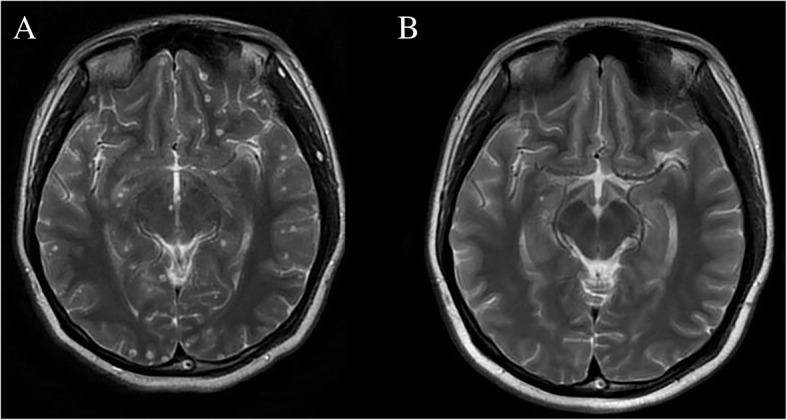

Systemic oral albendazole and steroid treatment were initiated after the ophthalmic operation. In the first course, albendazole at a quarter of the total dose (20 mg/kg body weight daily, three times a day for 10 days) during the first course with 5 mg of intravenous dexamethasone was given daily. An acute response was observed on the third day, which was attributed to local inflammation due to the larvae death. The intravenous dose of dexamethasone was increased to 10 mg daily until albendazole treatment was discontinued. The patients received albendazole at a total dose of 20 mg/kg body weight daily for 10 days, and another two courses of albendazole equal dose with 3 months treatment interval. Most of cysts, especially intraparenchymal cysts, were disappeared (Fig. 3).

Fig. 3.

Comparison of neurocysticercosis lesions in the human brain before and after anti-parasitic treatment. a T2-weighted images showed numerous viable cysts before treatment. b A degenerating cyst in the right temporal lobe with most lesions disappeared after anti-parasitic treatment